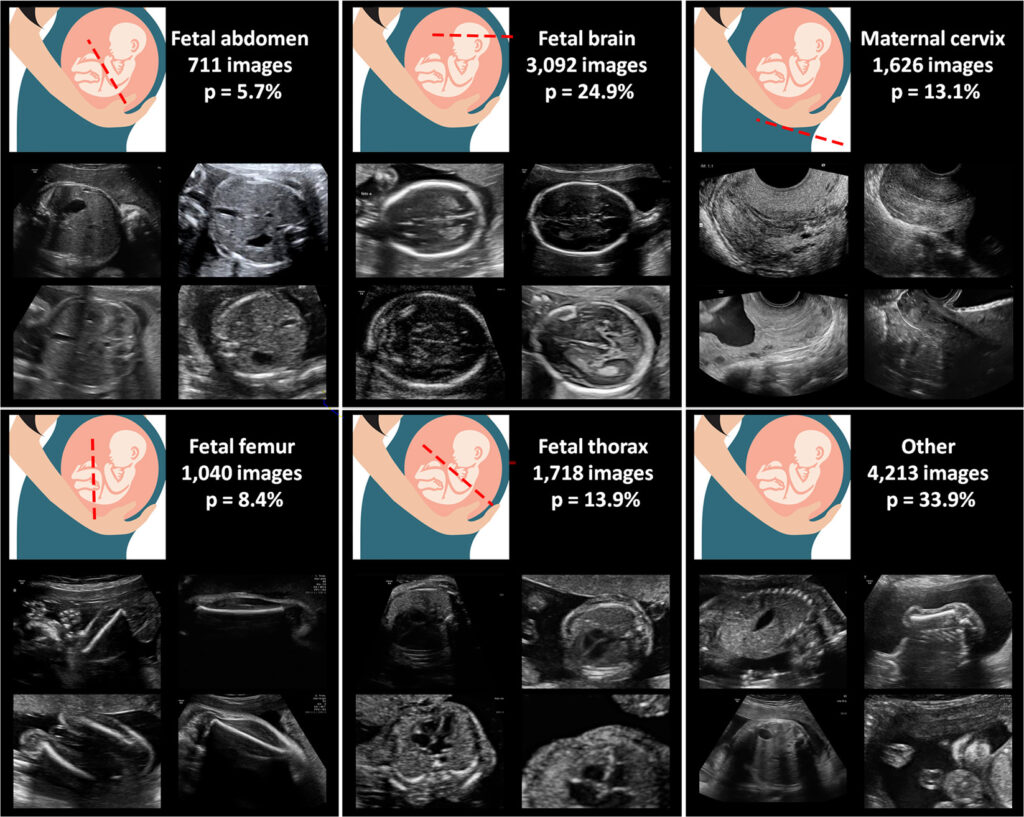

Siêu âm thai nhi là một phương pháp chuyên ngành sử dụng sóng siêu âm để tạo ra các hình ảnh của thai nhi trong tử cung. Đây là một công cụ quan trọng trong quá trình chăm sóc thai kỳ, được sử dụng để đánh giá sự phát triển, sức khỏe của thai nhi, kiểm tra cấu trúc cơ bản và xác định vị trí của thai nhi trong tử cung.

Siêu âm thai nhi thường được thực hiện trong quá trình mang bầu, bắt đầu từ tuần thứ 6 đến tuần thứ 40 của thai kỳ. Thời điểm cụ thể phụ thuộc vào mục đích của siêu âm và chỉ định từ bác sĩ. Dưới đây là một số chỉ số quan trọng cần lưu ý trong quá trình thực hiện siêu âm thai nhi:

- Chiều dài xương đùi của thai nhi: Kích thước của xương đùi có thể đưa ra thông tin về tuổi thai, tốc độ tăng trưởng và sự phát triển tổng thể của thai nhi. Đường cong tăng trưởng của chiều dài xương đùi cũng có thể giúp xác định nếu có bất thường trong sự phát triển thai nhi.